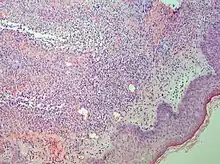

Studies show a moderate neutrophilia (less than 50%), elevated ESR (greater than 30 mm/h) (90%), and a slight increase in alkaline phosphatase (83%). Skin biopsy shows a papillary and mid-dermal mixed infiltrate of polymorphonuclear leukocytes with nuclear fragmentation and histiocytic cells. The infiltrate is predominantly perivascular with endothelial-cell swelling in some vessels, but vasculitic changes (blood clots; deposition of fibrin, complement, or immunoglobulins within the vessel walls; red blood cell extravasation;inflammatory infiltration of vascular walls) are absent in early lesions.Perivasculitis occurs secondarily, because of cytokines released by the lesional neutrophils. True transmural vasculitis is not an expected finding histopathologically in SS.